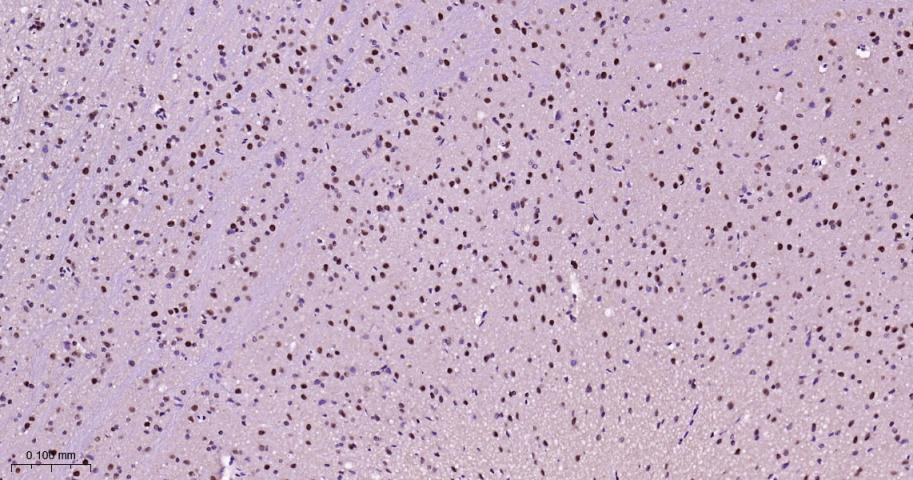

Paraformaldehyde-fixed, paraffin embedded Human Brain; Antigen retrieval by boiling in sodium citrate buffer (pH6.0) for 15 min; The section was incubated with HP1 gamma Monoclonal Antibody, Unconjugated(bsm-61603R) at 1:200 overnight at 4°C, followed by conjugation to the bs-0295G-HRP and DAB (C-0010) staining.

Paraformaldehyde-fixed, paraffin embedded Rat brain; Antigen retrieval by boiling in sodium citrate buffer (pH6.0) for 15 min; The section was incubated with HP1 gamma Monoclonal Antibody, Unconjugated(bsm-61603R) at 1:200 overnight at 4°C, followed by conjugation to the bs-0295G-HRP and DAB (C-0010) staining.

Paraformaldehyde-fixed, paraffin embedded Mouse brain; Antigen retrieval by boiling in sodium citrate buffer (pH6.0) for 15 min; The section was incubated with HP1 gamma Monoclonal Antibody, Unconjugated(bsm-61603R) at 1:200 overnight at 4°C, followed by conjugation to the bs-0295G-HRP and DAB (C-0010) staining.